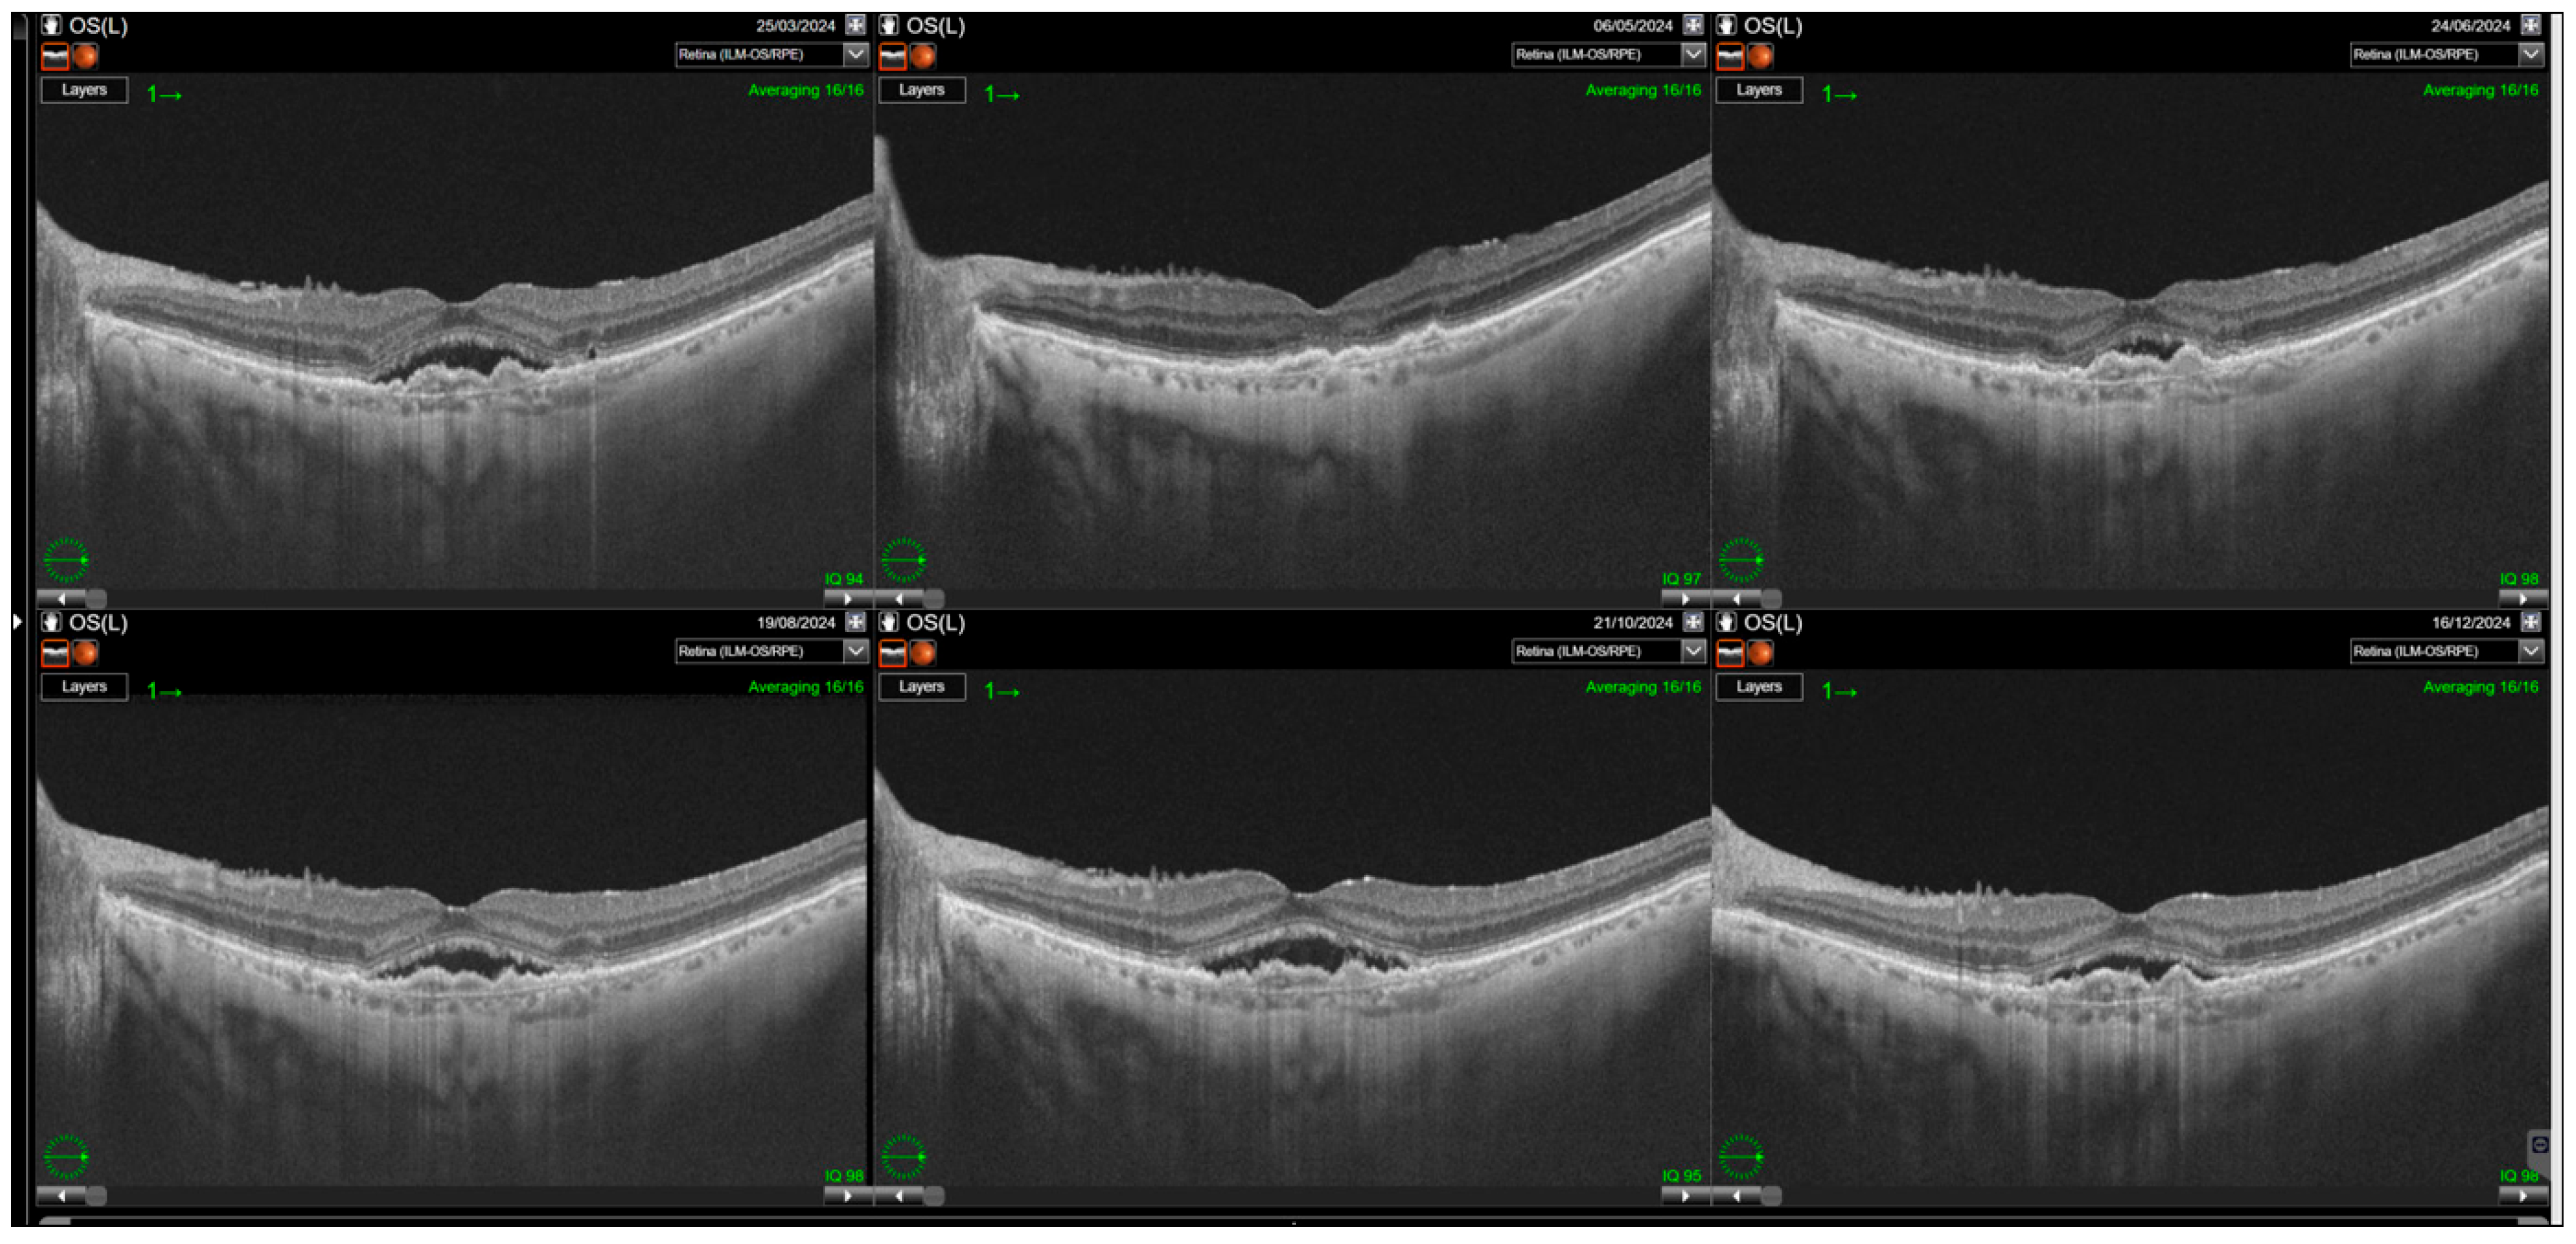

Switching to faricimab in the treatment of nAMD produced anatomical improvements that followed a distinct temporal pattern during post-switch follow-up. By the end of the observation period, retinal morphology demonstrated clear improvement, driven primarily by a reduction in SRF. In contrast, changes in IRF were not statistically significant, while reductions in PED reached borderline statistical significance at the final visit (p = 0.0455). The greatest morphological benefit was observed at visits 2 and 3, corresponding to the second phase of the loading regimen, during which the reduction in residual IRF was also statistically meaningful. However, as treatment intervals were subsequently extended, the magnitude of these anatomical gains gradually declined (Table 2). Loss of early improvement after the loading phase was also evident in SS-OCT parameters, specifically CST (Table 3; Figure 1). Retinal thickness showed a significant reduction compared with baseline during the loading phase, but this benefit gradually waned and was no longer present at the end of follow-up. Examples of SS-OCT scans at baseline and through the follow-up are presented in Figure 2 (good response) and Figure 3 and Figure 4 (poor response).

Figure 2. Significant improvements in retinal morphology noted through the follow-up. Complete resolution of subretinal fluid (SRF) and intraretinal retinal fluid (IRF) is noted through the whole observation time post first injection.